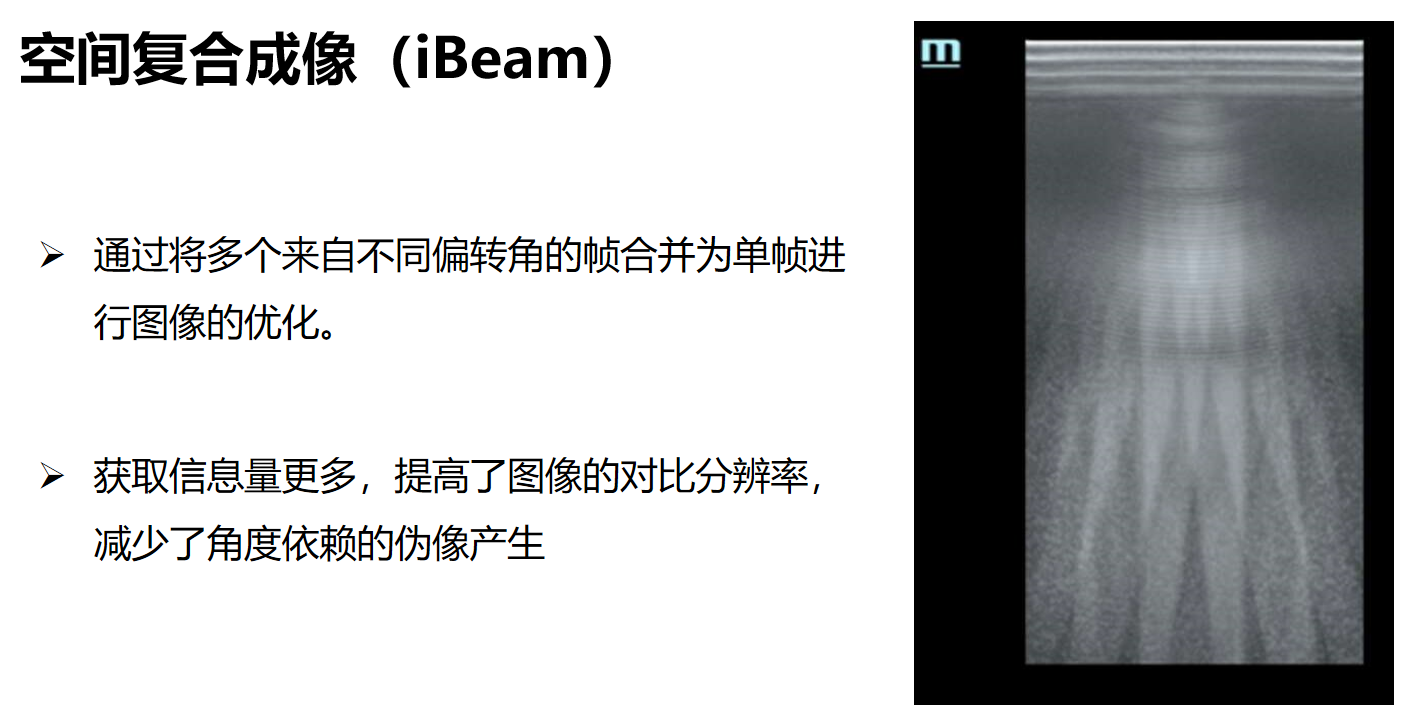

空间复合成像(iBeam)使用数字电子声束偏转技术,发射多束不同角度声波,接收多角度多线图像合并为单帧,进行图像的优化。他可以获取更多信息量,提高图像的对比分辨率,减少角度依赖,打开后的图像具有斑点噪声减少,图像清晰的特点,提高了对比分辨率,更容易显示病灶位置。但是一般在有结石的情况下不适合使用。